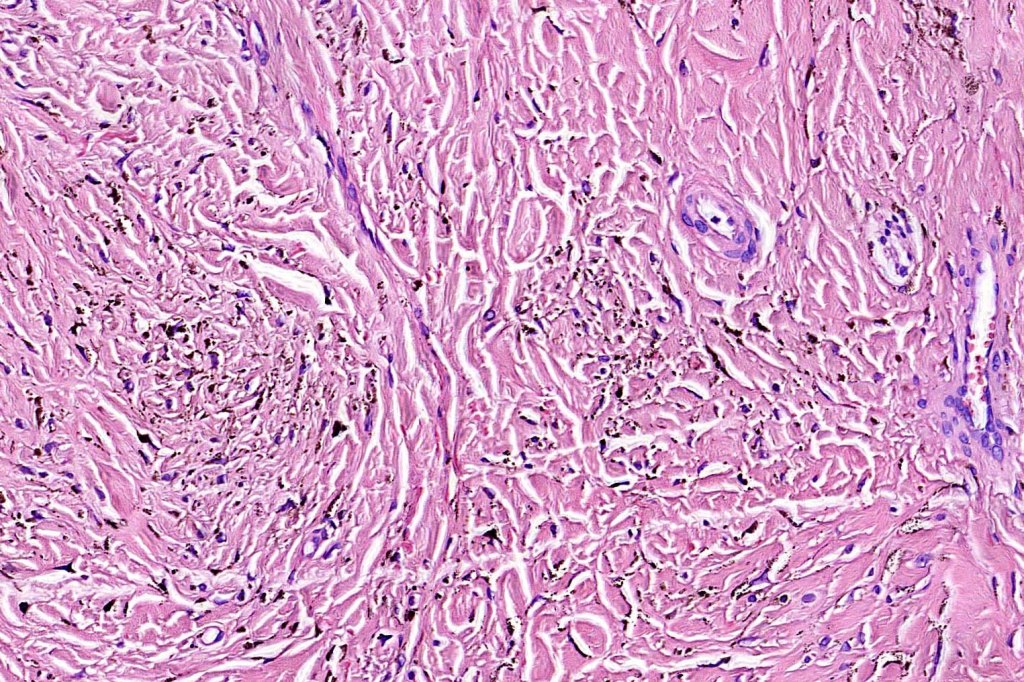

Histologically, it is characterized by a dense population of spindled, dendritic melnanocytes & melanophages with variable fibrosis. It may sometimes represent a component of a combined nevus. Mitotic activity is not usually present and pleomorphism is absent (see atypical blue nevus below). Involvement of the arrector pili muscle is not uncommon.

Very exceptionally, blue nevus also involves the epidermis (compound blue nevus).